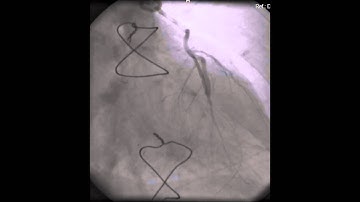

LIMA to LAD Graft